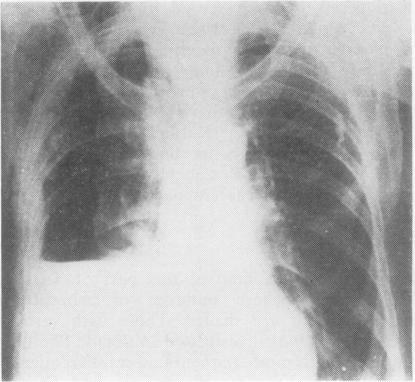

透闪石粉尘导致的胸膜钙化、胸膜间皮瘤和支气管癌。

Pleural calcification, pleural mesotheliomas, and bronchial cancers caused by tremolite dust.

Around the town of Cermik in south-east Turkey there are many deposits of asbestiform minerals, some of which are used to make whitewash or stucco. A sample of 7000 of the population revealed 461 (6.5%) with pleural thickening and calcification, of whom 103 (1.47% of the total) had evidence of interstitial pulmonary fibrosis. Forty-one patients with respiratory cancer were admitted to the Diyarbakir Chest Hospital from around Cermik and from a comparable area of equal population (but without asbestos deposits) in 1977-8. Of these 23 were mesotheliomas, 22 coming from around Cermik. In addition, 11 of the 18 primary bronchial cancers came from around Cermik. A similar excess of mesothelioma and bronchial cancer had been admitted from the Cermik area in previous years. The whitewash or stucco material has been shown to contain fibrous tremolite and non-fibrous antigorite/lizardite, chlorite, and talc. A lung biopsy of a patient from Cermik contained large numbers of tremolite fibres, both free and forming asbestos bodies. There were only occasional chrysotile fibres.

在土耳其东南部的塞尔米克镇周围,有许多石棉状矿物矿床,其中一些被用于制作石灰浆或灰泥。对7000名居民的抽样调查显示,有461人(6.5%)出现胸膜增厚和钙化,其中103人(占总人数的1.47%)有间质性肺纤维化的迹象。1977年至198年期间,有41名来自塞尔米克镇周边以及人口相当的类似地区(但没有石棉矿床)的呼吸道癌症患者被收治进迪亚巴克尔胸科医院。其中23例为间皮瘤,22例来自塞尔米克镇周边。此外,18例原发性支气管癌中有11例来自塞尔米克镇周边。往年从塞尔米克地区收治的间皮瘤和支气管癌患者也有类似的超额情况。已证明石灰浆或灰泥材料中含有纤维状透闪石以及非纤维状叶蛇纹石/纤蛇纹石、绿泥石和滑石。一名来自塞尔米克镇的患者的肺活检显示含有大量游离的和形成石棉小体的透闪石纤维。只有偶尔的温石棉纤维。